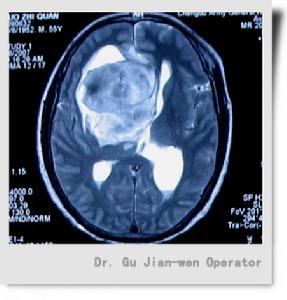

松果體區腫瘤MRI顯示圖松果體瘤導致性早熟可能由於腫瘤壓迫或破壞影響下丘腦的調節功能或HCG的分泌。神經內分泌解剖結果認為,由於腦的其他腫瘤擴大延伸到松果體引起性早熟。

松果體區腫瘤MRI顯示圖松果體的節律性活動可概括為3種:①近日節律:指MLT合成分泌呈24h周期性變化, 影響松果體MLT近日節律的主要生理因素是光照的刺激。受夜間暗光刺激信號使MLT高峰值在夜晚。②月節律:女性血中MLT波動與月經周期同步,月經來潮時,MLT升高至排卵前5倍左右,排卵前LH達高峰,MLT水平則降到最低。MLT下降對排卵可能起“允許”作用。③年度節律:生殖年度的特點是生殖力的高潮與垂體,性腺系統靜止交替出現, 這一交替現象可能由於日照期長短通過松果體影響生殖系統而實現的。

圖1 松果體區腫瘤1.腦水腫 松果體區域的腫瘤侵入第三腦室,致使阻塞,引起顱內壓升高, 常見症狀為昏睡、頭痛、嘔吐、精神異常。一般來說,阻塞越急劇,症狀發生越突然 越明顯。

松果體區腫瘤的診斷必須以病理組織學分類為依據 因為各型腫瘤的治療方案和預後差別很大,而最大的困難還是很難獲得組織學標本,因而強調立體定向松果體區病變活檢的重要性(圖1)。

2.MRI對松果體母細胞瘤診斷有獨到優點,松果體母細胞瘤起源於松果體腺, 惡性程度大,具浸潤性, 生長快,易轉移,病人存活期短, 因而早期診斷治療十分重要, MRI顯示松果體腫瘤區域的高信號以及清晰可見腫瘤侵入第三腦室的程度。